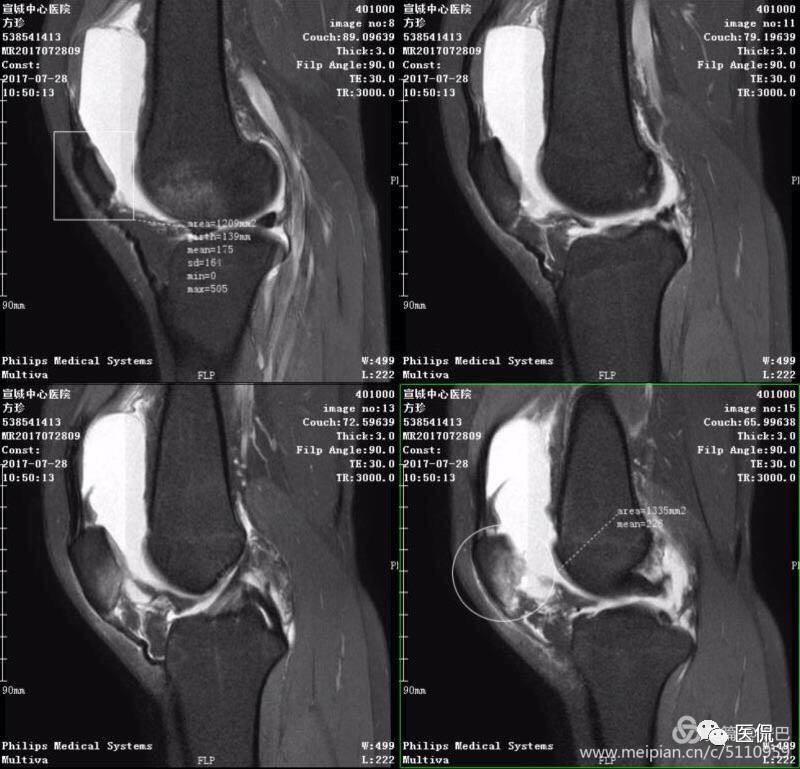

MR表现

1、单液-液平面:上层呈短T1、长T2信号、T2压脂像低信号、Pd像呈高信号;下层呈中等T1、T2信号、T2压脂像和Pd像呈较高信号。

2、双夜-液平面:上层呈短T1、长T2高信号、T2压脂像低信号、Pd像呈高信号;中层呈长T1、长T2信号、T2压脂像和Pd像呈较高信号;下层呈中等T1、T2信号、T2压脂像和Pd像呈较高信号。

3、多液-液平面:最上层呈无信号区;上层呈短T1、长T2高信号、T2压脂像低信号、Pd像呈高信号;中层呈长T1、长T2信号、T2压脂像和Pd像呈较高信号;下层呈中等T1、T2信号、T2压脂像和Pd像呈较高信号。